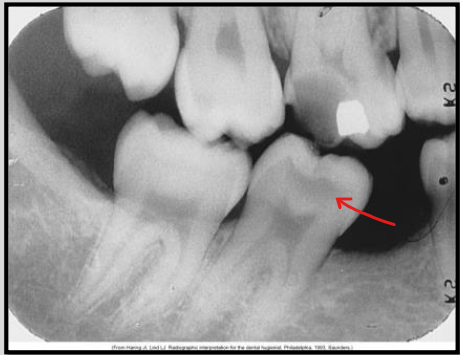

What class of interproximal caries is this?

Class 1 - incipient lesion

Class 2 - Moderate

Class 3 Advanced

Class 4 Severe